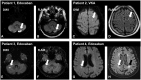

Methods and results: The ELIMINATE-AF trial, a multinational, multicentre, randomized, open-label, parallel-group study, was conducted to assess the safety and efficacy of once-daily edoxaban 60 mg (30 mg in patients indicated for dose reduction) vs. vitamin K antagonists (VKAs) in AF patients undergoing catheter ablation. Patients were randomized 2:1 to edoxaban vs. VKA. The primary endpoint (per-protocol population) was time to first occurrence of all-cause death, stroke, or International Society of Thrombosis and Haemostasis-defined major bleeding during the period from the end of the ablation procedure to end of treatment (90 days). Overall, 632 patients were enrolled, 614 randomized, and 553 received study drug and underwent ablation; 177 subjects underwent brain magnetic resonance imaging to assess silent cerebral infarcts. The primary endpoint (only major bleeds occurred) was observed in 0.3% (1 patient) on edoxaban and 2.0% (2 patients) on VKA [hazard ratio (95% confidence interval): 0.16 (0.02-1.73)]. In the ablation population (modified intent-to-treat population including patients with ablation), the primary endpoint was observed in 2.7% of edoxaban (N = 10) and 1.7% of VKA patients (N = 3) between start of ablation and end of treatment. There were one ischaemic and one haemorrhagic stroke, both in patients on edoxaban. Cerebral microemboli were detected in 13.8% (16) patients who received edoxaban and 9.6% (5) patients in the VKA group (nominal P = 0.62).